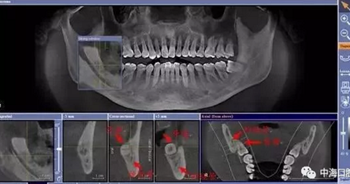

由于智齒的生長位置特殊,導(dǎo)致了拔除難易不同,如智齒出現(xiàn)橫著長或者靠近牙神經(jīng)的話,則難度會較高,一般人只需拍個口腔全景片,但相對于智齒靠近神經(jīng)管的情況,還可能需要拍CT,這都很考驗牙醫(yī)的技術(shù)。

下面這兩張圖,據(jù)說拔牙費時1.5小時,收費14000元。